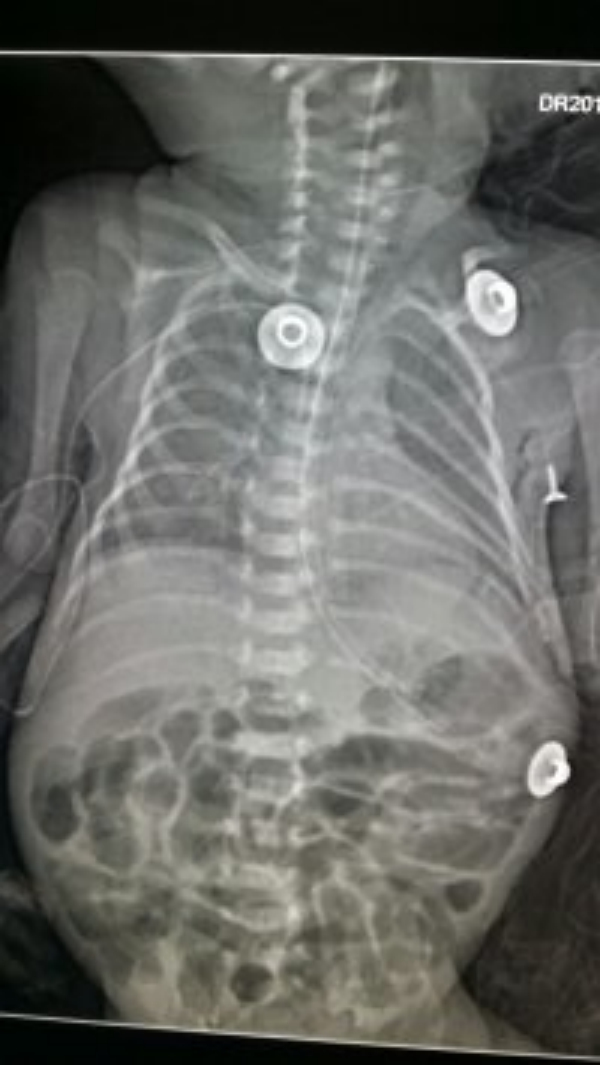

2015.7.9日,在新生儿科刘艳主管护师的全程指导及配合下,桂艳红护师与张静护师成功为体重仅1.0千克的刘甜之女PICC置管成功,从用物准备到床旁X线摄片显示导管末端位置准确,用时前后不到三十分钟;7.13日,7.29日,三人再次强力组合,为体重也仅1.0千克左右的雷苏军之子、1.1千克的文妙妙之子PICC置管成功。